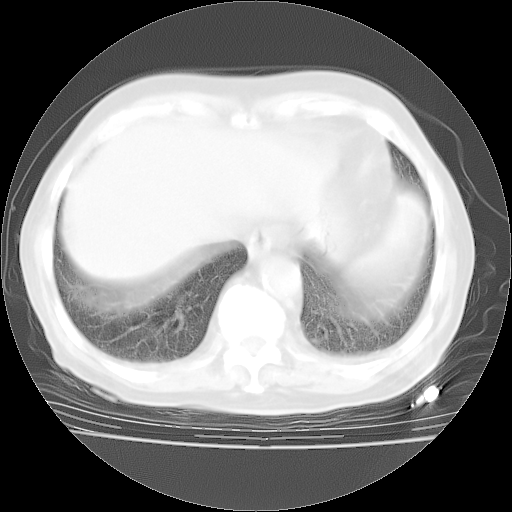

4月28日肺部CT——再次出现类似去年5月9日——透光度降低,“间质性”改变。

个人阅读4.14日肺部CT平扫:纵隔窗无异常,但肺窗示:双下肺内、后基底段有片絮状侵润影,部位以后基底段为著,以间质改变为主,呈急性肺泡炎征像,和首次住院影像学有相似之处。仅是个人读片,明日请相关专家再读片哈。其它建议同上。

1、108#的是4月14日的胸部CT(发此贴时还没看着28日的CT)。14日的胸部CT其实已经出现改变(如108#所述),个人认为28日的胸部CT除纵膈窗疑似有双侧胸膜增厚或少量胸积液(可行胸部B超明确)外,与4月14日对照病变有所加重;2、已经给予“异烟肼、利福平、乙胺丁醇”抗痨治疗?如果是,甲强龙80mg可缓慢减量;如果环磷酰胺已停用,暂不使用;3、中性粒细胞92%,明显升高,目前体温情况?注意合并细菌感染可能,使用左氧氟沙星情况下,是否联用B-内酰胺类抗菌药物?另外是查免疫全套非风湿全套。

今请临免主任会诊后认为:4月14日胸部CT已有双下肺间质性改变。患者病情复发多系激素减量过快不正规所致。目前甲强龙80mg/日,一周后酌情开始减量,不易过快。环磷酰胺若已停用,暂不使用。他同意目前抗菌药物使用,但应考虑是否加用B-内酰胺类抗菌药物(中性细胞明显增高);2、结核复发目前依据不足;3、若免疫全套各项指标正常,考虑多系特发性肺间质炎可能大。4、加强支持,并注意保护胃黏膜。

今上午去请教了临免、呼吸主任:1、介绍病史和阅读系列胸部CT一致认为:患者肺结核不考虑,仍为肺间质纤维化,目前处于急性肺泡炎阶段。2、若仍发热,可将甲强龙增至:80mg Bid静滴,同时鉴于中性增高,合并细菌感染可能,继续左氧氟沙星治疗,再联用B-内酰胺抗菌药物,如头孢哌酮--舒巴坦;3、停用抗痨药;4、目前甲强龙每日剂量160mg ,体温正常后再酌情减量;目前暂不用免疫抑制剂;4、不建议使用免疫增强剂等;5、加强支持治疗,鼓励患者进食;5、注意随访肝、肾功及血常规情况;6、因患者目前激素用量较大,加用胃黏膜保护剂,防止消化道出血可能。